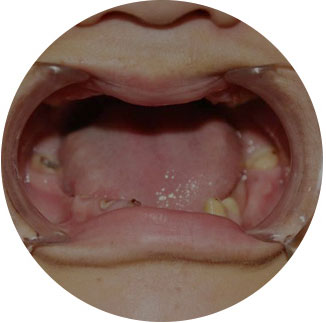

骨量严重萎缩的情况下,利用斜行植体等技术,避免植骨手术。

可以解决全口、半口无牙颌、 牙槽骨严重萎缩/极薄问题。